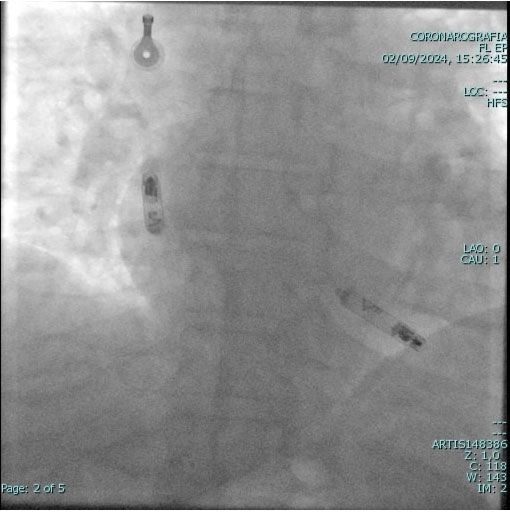

Il SEFE viene effettuato previo breve ricovero e prevede l'esecuzione di un'anestesia locale delle vie di accesso, generalmente queste sono: la vena femorale destra a livello dell'inguine, oppure la vena succlavia sinistra a livello della spalla; più raramente è possibile eseguire l'esame attraverso la vena giugulare del collo. Vengono inseriti nel cuore da 2 a 5 elettrocateteri morbidi, che vengono posizionati all'interno delle cavità cardiache (generalmente in atrio e ventricolo destro, sul fascio di His e, se necessario, all'interno del seno coronarico), che registrano i segnali elettrici originati dalle cavità cardiache.

L' ablazione trans-catetere viene eseguita in anestesia locale (come quella che usa il dentista). Attraverso una vena e/o un'arteria della coscia, che passa in regione inguinale (se necessario viene a volte utilizzata anche una vena del braccio o una vena sotto la clavicola sinistra), vengono introdotti dei fili elettrici (i cosiddetti “elettro-cateteri”) e guidati, sotto controllo radiologico, fino all'interno delle cavità cardiache; tale manovra è assolutamente indolore e non viene avvertita dal paziente.

Una volta posizionati nelle cavità cardiache, i cateteri sono collegati a particolari apparecchiature che registrano l'attività elettrica all'interno del cuore; tutto ciò è completamente indolore, come un qualsiasi elettrocardiogramma.

Durante l'ablazione è necessario stimolare il cuore con piccolissimi impulsi elettrici emessi dai cateteri (non percepiti dal paziente), in modo da poter provocare l'aritmia in esame e identificare la zona da cui ha origine. Con opportuni stimoli elettrici l'aritmia può essere interrotta dall'operatore. Una volta identificato il punto di origine dell'aritmia, si procede all'ablazione propriamente detta: mediante uno dei cateteri, già presenti all'interno delle cavità cardiache, si trasmette una particolare corrente elettrica, chiamata “radiofrequenza”, che scalda la punta del catetere stesso (la temperatura non va mai oltre i 60 gradi); il calore determina la coagulazione del punto responsabile dell'aritmia, che viene, in tal modo, soppresso.